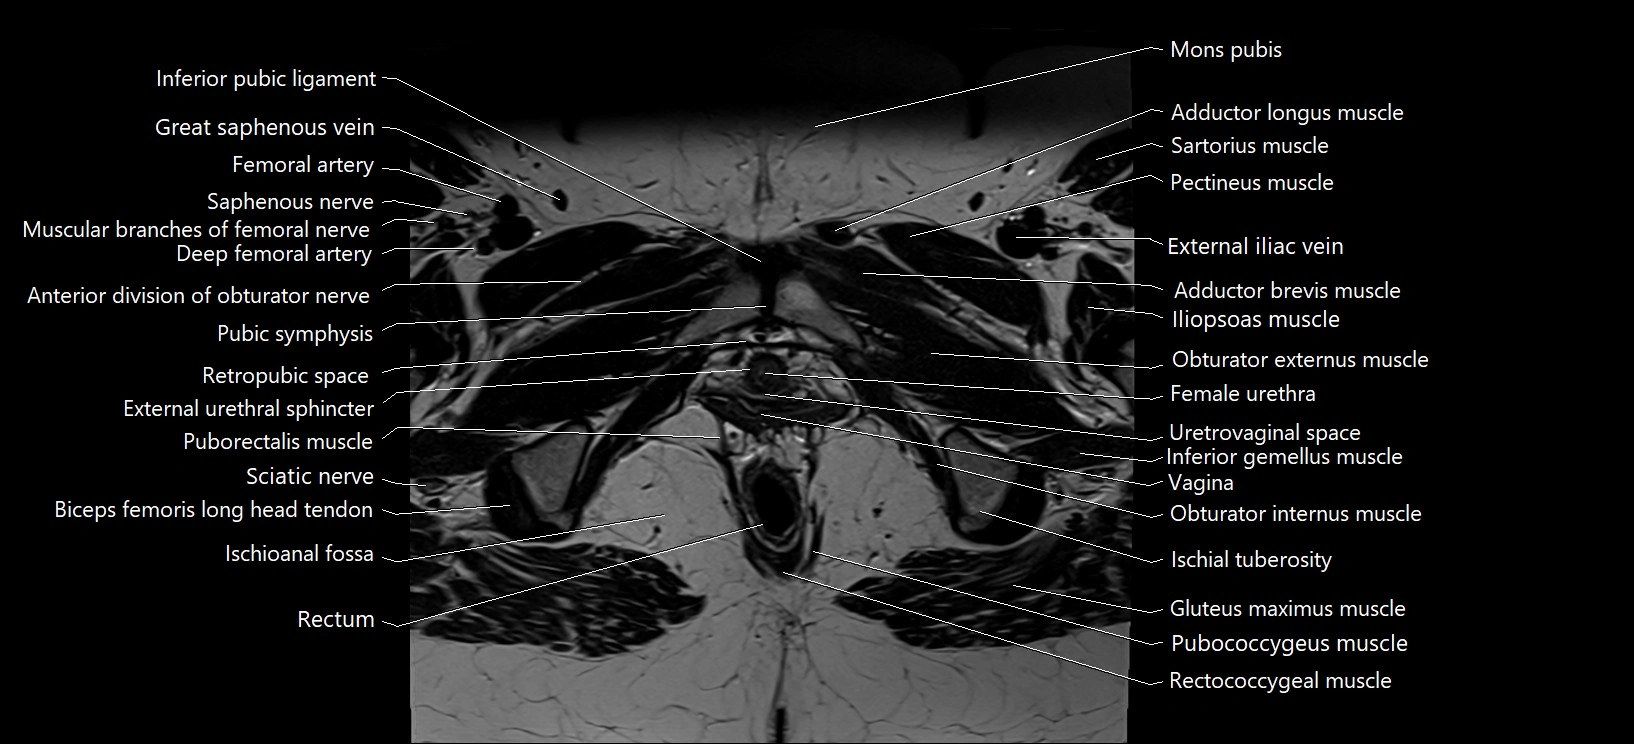

- Anterior division of obturator nerve (Anterior branch of obturator nerve)

- Deep femoral artery (profunda femoris)

- External urethral sphincter (female)

- Female urethra

- Femoral artery

- Femoral nerve

- Gluteus maximus muscle

- Gracilis muscle

- Inferior gemellus muscle

- Inferior pubic ligament

- Ischioanal fossa

- Mons pubis

- Muscular branches of femoral nerve

- Obturator externus muscle

- Obturator internus muscle

- Pectineus muscle

- Pubic symphysis

- Pubococcygeus muscle

- Puborectalis muscle

- Rectococcygeal muscle

- Rectum

- Retropubic space

- Saphenous nerve

- Sartorius muscle

- Sciatic nerve

- Vagina